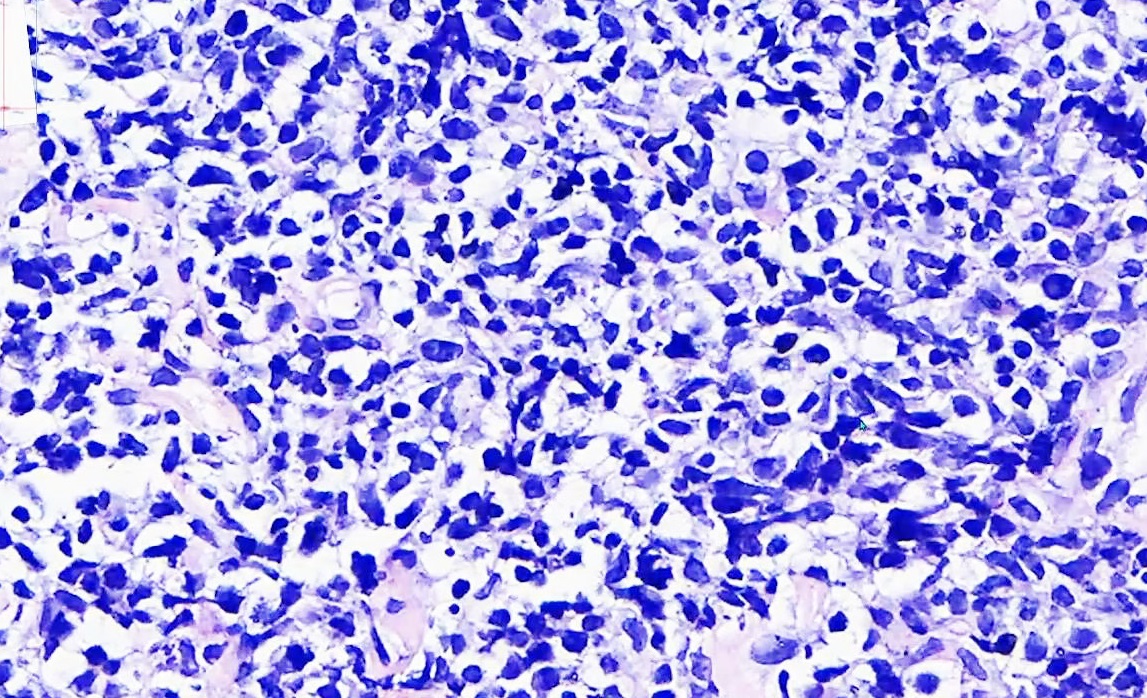

右小腿肿瘤4个月 活

右小腿肿瘤4个月 活检组织 一致性淋巴样细胞增生 有凋亡细胞碎片 淋巴瘤 类型需要免疫组化标记